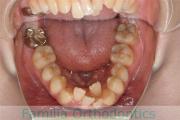

No.22V-029

- 叢生

- 上顎前突

- 19歳

- 男性

- 上:

- 8448

- 下:

- 主な使用装置:

- FEA 022

- 治療にかかった費用:

- 92万円

でこぼこを治したいということで来院されました。上下左右から親知らずも第一小臼歯も抜歯が必要で、歯科矯正アンカースクリューを併用して大臼歯を後ろに引っ張りながらの治療でした。3年弱、35回程度の通院が必要でした。

叢生が著しく、後戻りのリスクがあります。またアンカースクリューが必須のため、もしもスクリューが安定しないと、治療が難しく長くなってしまう恐れがありましたが、幸い脱落は見られませんでした。